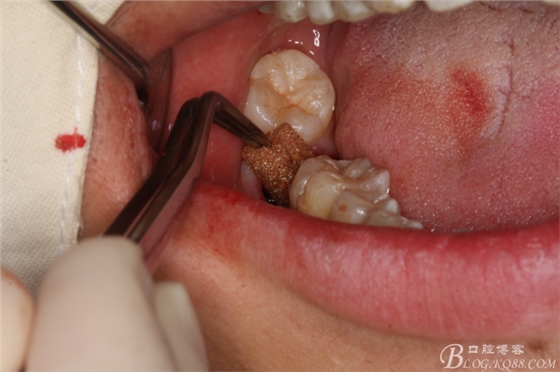

圖7.不切開(kāi)、不翻瓣、利用有限空間直接高速牙鉆分牙

圖8.先橫斷47牙冠,盡量從牙頸部橫斷

圖9.潛掘法橫斷牙冠